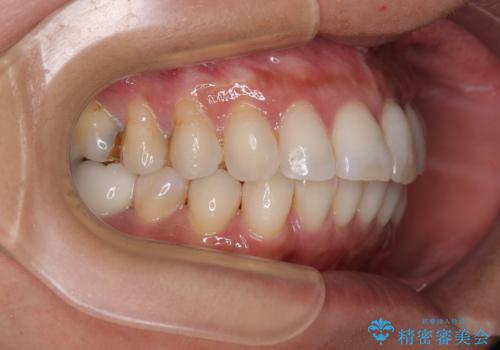

しっかりと装着時間を守ってくださり、来院のタイミングに合わせてインビザラインの装着期間を調整するなど、協力いただいたおかけで、1年半の期間で全てを終えることができました。